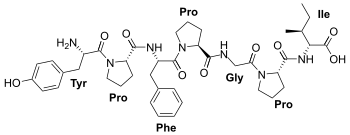

Opioid peptides

Endomorphins

Endorphins

Structures

Enkephalins

Structures

| Enkephalins | ||||

|---|---|---|---|---|

DAMGO DAMGO |

||||

Propeptides

Others / unknown

- Adrenorphin

- Amidorphin

- Biphalin

- Casokefamide

- Casomorphins

- Cytochrophin-4

- DALDA (Tyr-D-Arg-Phe-Lys-NH2)

- Deltorphin I

- Deltorphin II

- Deprolorphin

- Dermorphin

- DPDPE

- Frakefamide

- Gliadorphin

- Gluten exorphins

- Hemorphin-4

- Metkefamide

- Morphiceptin

- Nociceptin

- Octreotide

- Opiorphin

- Rubiscolin

- Soymorphins

- Spinorphin

- TRIMU 5

- Tynorphin

- Valorphin

- Zyklophin

Structures

| Other or unknown opioid peptides | ||||

|---|---|---|---|---|

Adrenorphin Adrenorphin |

Amidorphin Amidorphin |

Casomorphin Casomorphin |

DALDA DALDA |

|

DPDPE DPDPE |

Endomorphin-1 Endomorphin-1 Endomorphin-2 Endomorphin-2 |

Gliadorphin Gliadorphin |

Morphiceptin Morphiceptin | |

Nociceptin Nociceptin |

Octreotide Octreotide |

Opiorphin Opiorphin |

Rubiscolin Rubiscolin |

TRIMU 5 TRIMU 5 |

Others